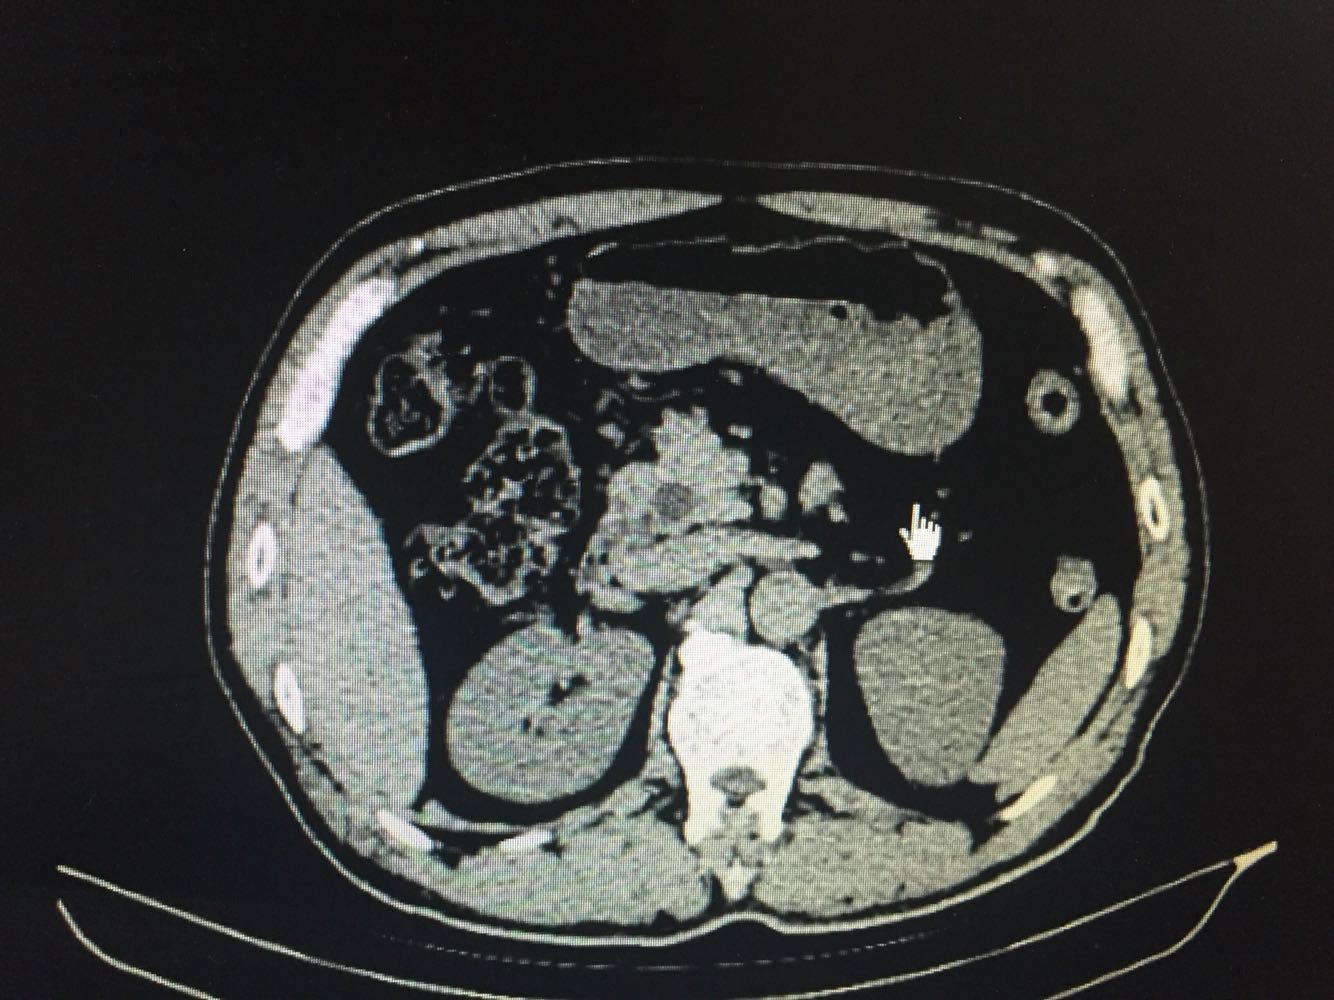

巩膜及皮肤黄染,上腹部稍韧,深压痛,余无明显异常。 上腹部CT提示胆总管扩张伴下端结石,胆囊炎症改变。血生化提示胆红素升高,以直接胆红素为主,转氨酶明显升高。

微创手术确实给病人带来很多受益 术前阅片见下端结石梗阻 术中取石很顺利 出于保险起见 还是没有直接缝合胆总管 留置了T管